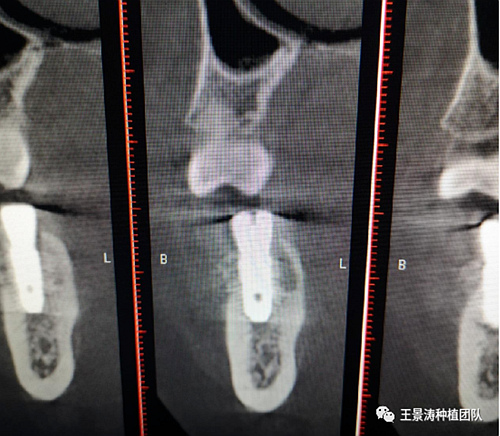

下述病例則是15區(qū)域的即刻種植,15因牙冠折斷于齦下,無法樁核冠修復(fù),則考慮種植修復(fù)。但拍攝CBCT后發(fā)現(xiàn)根尖距上頜竇底距離較短?;颊邽槟贻p女性,無全身系統(tǒng)疾病且可利用上頜竇底與根尖皮質(zhì)骨雙側(cè)皮質(zhì)骨固位,且此位置可通過頰側(cè)軟組織減張技術(shù)獲得嚴(yán)密封閉牙槽窩。因其根尖距上頜竇距離較低,遂拔除15后行上頜竇內(nèi)提升,埋入式種植,最終修復(fù)的完成。

(3)根尖周無急性炎癥,慢性炎癥存在的情況下,需評估根尖骨質(zhì)可否使植體獲得良好的三維位置和初期穩(wěn)定性,對于上頜后牙區(qū)來說,如果可以經(jīng)過上頜竇內(nèi)提升實現(xiàn)雙層皮質(zhì)骨固位,獲得較好的穩(wěn)定性也可以考慮即刻種植;而下頜后牙區(qū)則需要評估根尖區(qū)域至下牙槽神經(jīng)管的距離,是否適合植入種植體;